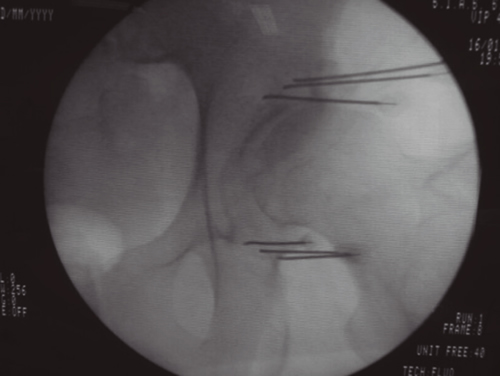

La neurotomía por radiofrecuencia del ramo medial es una técnica que está bien estandarizada a nivel cervical y lumbar, no así a nivel torácico, y que es un tratamiento que está bien establecido y estudiado con un nivel de evidencia alto (2,3,4). Por tanto, tras llegar al diagnóstico de dolor facetario el tratamiento de elección es la neurotomía por radiofrecuencia del ramo medial (Figuras 1 y 2).

Fig. 1.

Fig. 2.

La neurotomía por radiofrecuencia del ramo medial es una técnica estandarizada a nivel cervical y lumbar, con unos niveles de evidencia elevados y, por tanto, totalmente recomendable en el tratamiento del dolor facetario secundaria a la artrosis vertebral.